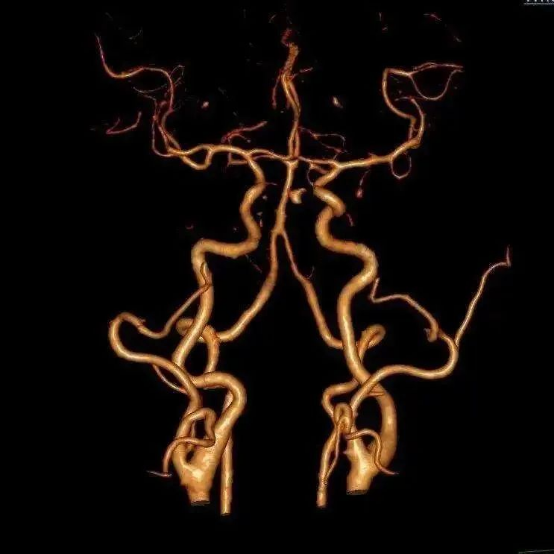

☆ 磁共振血管成像(MRA)的特点是无创、不需要注射造影剂就可以完成,可以在开展核磁共振检查时同时进行,但对脑血管疾病检查分辨率较差,可以作为脑血管疾病的筛查。

☆ CT血管成像(CTA)需注射含碘造影剂,在做之前需要了解肾功能情况(造影剂通过肾脏排泄),可以快速完成,病人痛苦少,分辨率较MRA有所提高,可以作为快速诊断脑血管疾病的方法及脑血管疾病的筛查。

☆ 全脑血管造影是最准确的脑血管造影方法,分辨率是最高的,是诊断脑血管疾病的“金标准”。在临床中,如果通过磁共振血管造影或CT血管造影检查,考虑有脑血管疾病的情况,特别是需要进一步治疗的时候,往往还是需要通过脑血管造影检查最后明确诊断,有些血管疾病在行脑血管造影检查的同时还可行介入治疗。